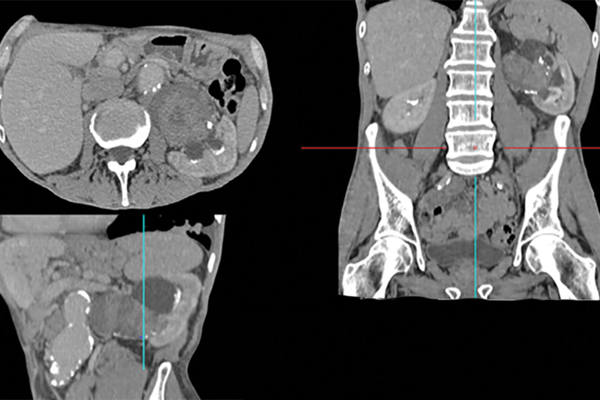

Assessment of the incidental adrenal lesion